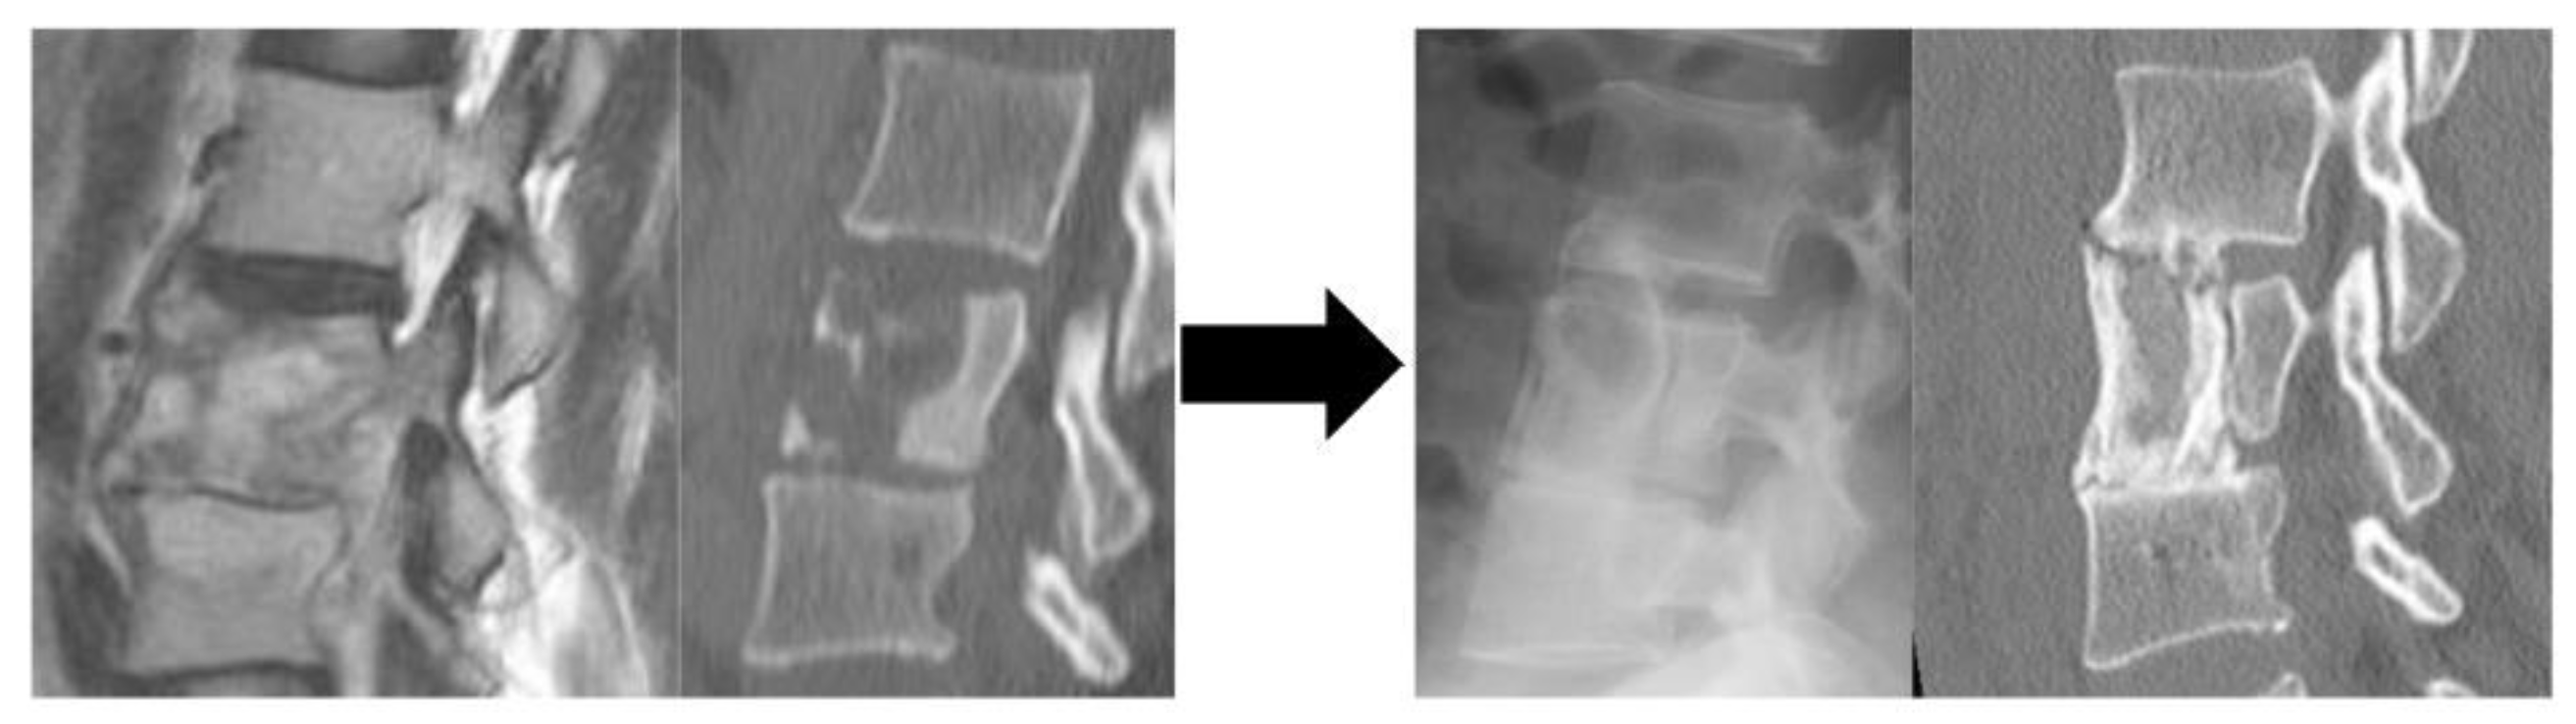

Figure 1.

A representative of Group A patients who underwent ASF alone and did not undergo reoperation during the course of the surgery. A Preoperative CT: bone destruction at the L3 and L4 vertebrae B Immediate postoperative X-ray: Trans retroperitoneal anterior scraping and iliac bone grafting. C Postoperative CT: Bone fusing at a year postoperatively. Abbreviation: CT, computed tomography; L, lumbar; ASF, anterior spinal fusion.